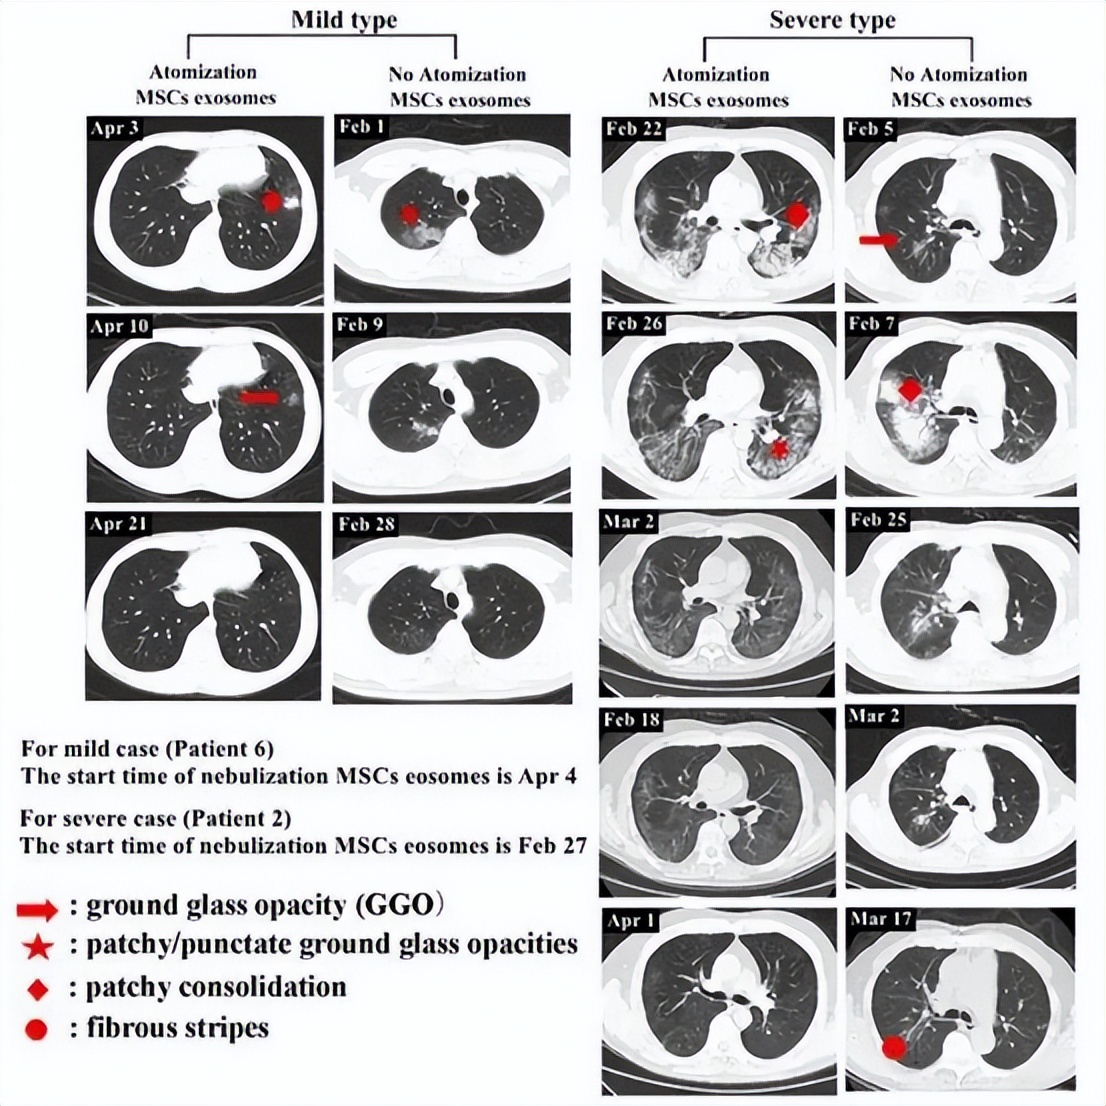

临床实践表明,雾化吸入外泌体能够有效促使肺结节体积缩小。其作用原理在于外泌体通过雾化途径直接抵达肺部,发挥其卓越的抗炎和组织修复功能,从而促使结节缩小。同时,其免疫调节能力有助于抑制结节的进展或恶变。

案例1: 某患者于2020年4月3日首次CT扫描显示左肺下叶外基底段存在一孤立性结节。接受外泌体雾化干预仅6天后(4月10日),CT复查即见结节密度减低、体积缩小。继续干预至第17天,该肺部病灶已完全吸收。

案例2: 另一患者自2020年2月27日开始接受外泌体雾化干预。至3月18日CT扫描显示双肺病灶已显著吸收,病灶密度明显减弱。到4月1日复查,肺部病灶实现完全吸收。值得对比的是,未接受外泌体干预的对照组患者,在病灶吸收后常遗留有纤维索条影。